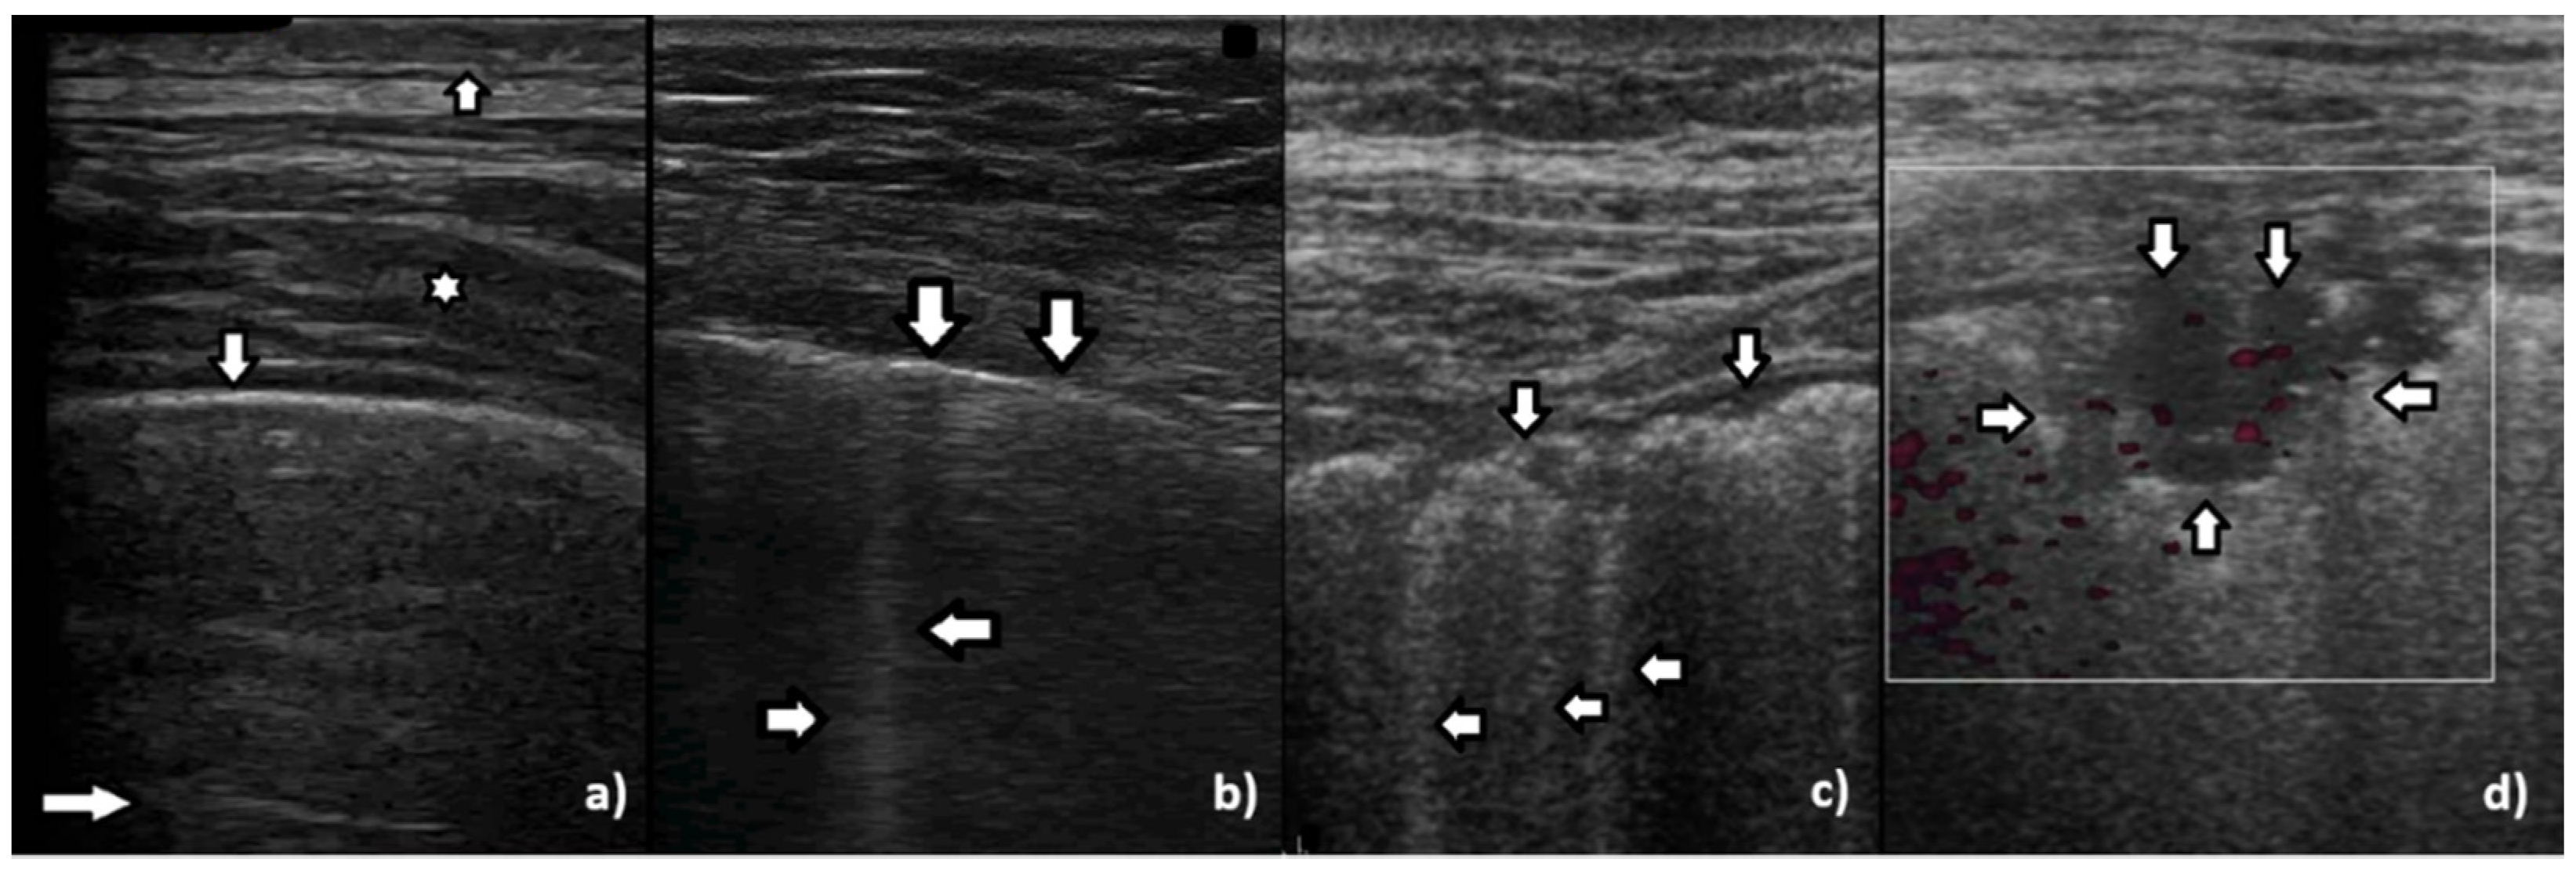

Based on clinical observations, we know that vertical artifacts can have different lengths, widths, and shapes (see Figure 5a–c). A modulation of artifacts is also often clearly perceived. Why are they so varied? What does this depend on?

Many types of acoustic traps exist, and, consequently, many types of vertical artifacts exist. Let us consider an isolated acoustic trap. It has its own volume and geometric shape. It is linked to the pleura plane by means of an acoustic channel (typically an interalveolar interstice), and this channel also has its own shape and size represented by its cross-section and length. Every single difference between two acoustic traps affects the visual aspect of the related artifacts. Moreover, you should never forget that even the imaging parameters (pulse central frequency and bandwidth, focus position, TGC, pulse amplitude, etc.) strongly affect the formation and the final shape of an artifact.

Figure 5. (a) Irregular, echoic pleural line (vertical arrows), long vertical artifact (left horizontal arrows), and shadow behind the rib (right horizontal arrows). The vertical artifact is classified as a B line since it originates from the pleural line and reaches the edge of the screen. Multiple small horizontal artifacts (named J artifacts by D. Lichtenstein) are visible inside the B line. (b) Smooth, regular, and echoic pleural line (vertical arrows), long vertical artifact, so called B line: narrow at the top and wide at the bottom (left and right horizontal arrows). (c) Smooth, regular, and echoic pleural line (vertical arrow), short vertical artifact, so called I line (left horizontal arrow and shadow behind the rib (right horizontal arrows).